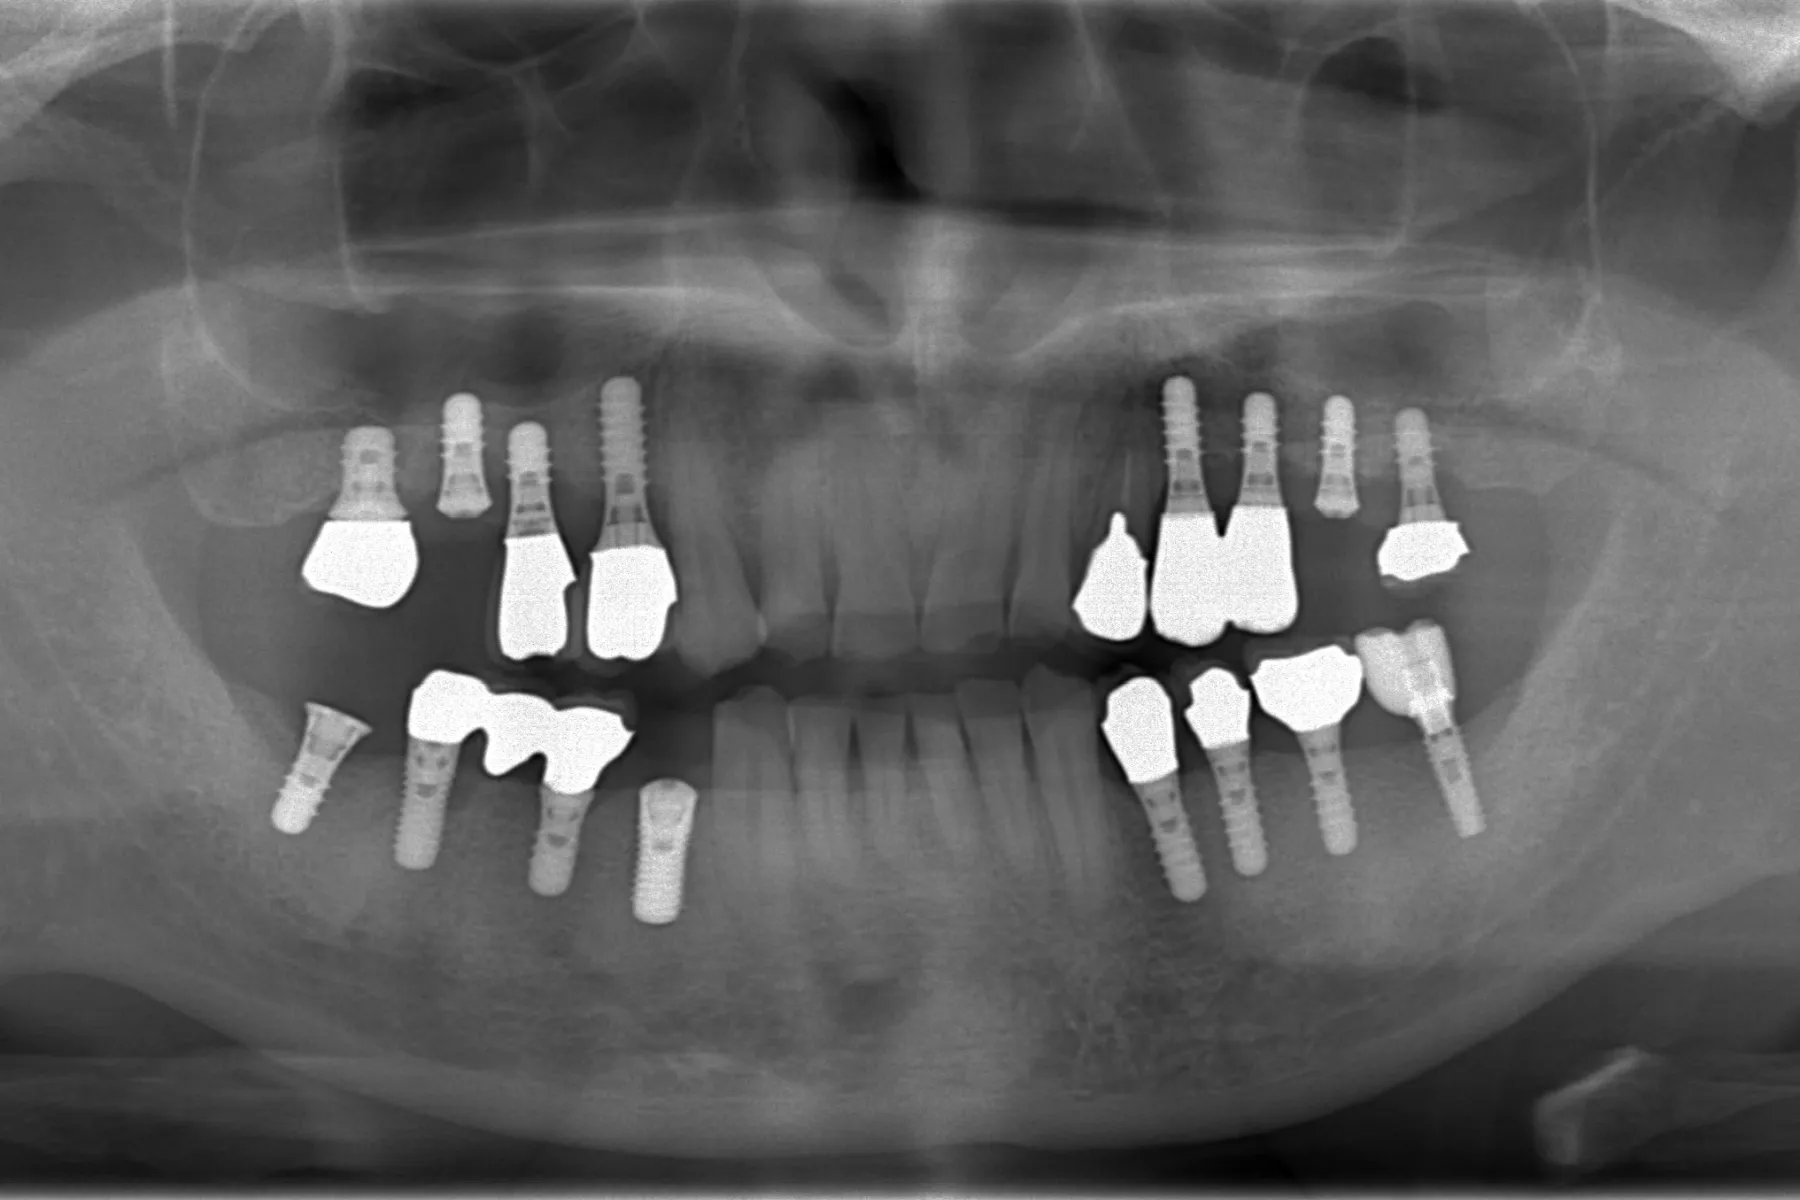

院長のレントゲン写真